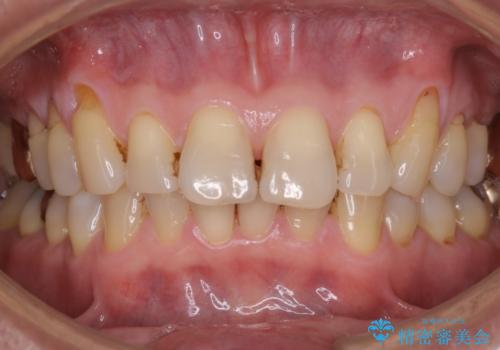

- 着色を落としてほしいとのことで1年ぶりに来院されました。

PMTC60分コースを行いました。

着色は、歯と歯の間と裏側に多く付いていました。

1年ぶりとなると、着色は層になり分厚く硬くなります。定期的にクリーニングをしてあげると良いかと思います。